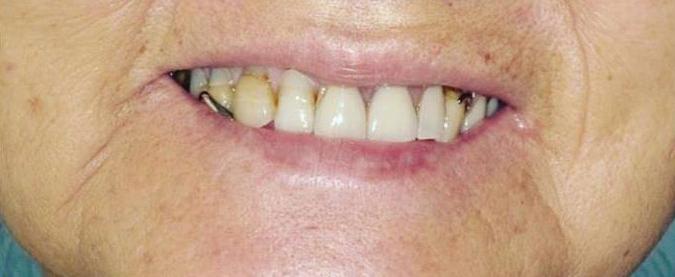

By Ali Ghatri, DDS Let’s Smile Dental

Dental implant procedures are complex and require the expertise of multiple dental professionals, each contributing their unique skills to achieve a successful and long-lasting result.

The general dentist typically serves as the primary point of contact. They initiate the diagnostic process, evaluate overall oral health, and determine whether the patient is a candidate for implants. The general dentist also handles initial care such as extractions, treatment of decay, or periodontal therapy. Once the need for collaboration is identified, the dentist coordinates referrals to the appropriate specialists.

An orthodontist may be involved early in the planning process, particularly if teeth have shifted into the space of a missing tooth or if bite alignment needs correction. Strategic tooth movement is often essential before implant placement, especially since implants, once placed, are immovable. Orthodontists use tools like braces or clear aligners to create optimal spacing and alignment, not just for aesthetics, but also to ensure the long-term success of the implant.

The oral surgeon is responsible for the surgical phase of treatment. This includes placing the titanium implant post into the jawbone with precision, sometimes performing additional procedures such as bone grafting or sinus lifts when necessary. Their goal is to ensure a solid foundation for the future res-

toration while minimizing surgical risk and promoting proper healing. In some cases, the oral surgeon may also consult with a periodontist to manage the health and shape of the gum tissue surrounding the implant. This is especially important in patients with a history of gum disease or when aesthetics are a priority in the smile zone.

Once the foundation is secure, the general dentist may work with a prosthodontist to design and place the final restoration—typically a crown, bridge, or denture. Prosthodontists specialize in restoring function and appearance with highprecision prosthetic teeth.

While collaboration between providers was introduced in the

first article, this second part highlights the distinct roles each professional plays during the process. The timing and sequence of care matter, and it’s often the general dentist who coordinates this multidisciplinary effort to ensure that every stage of treatment is integrated, efficient, and tailored to the patient’s needs.